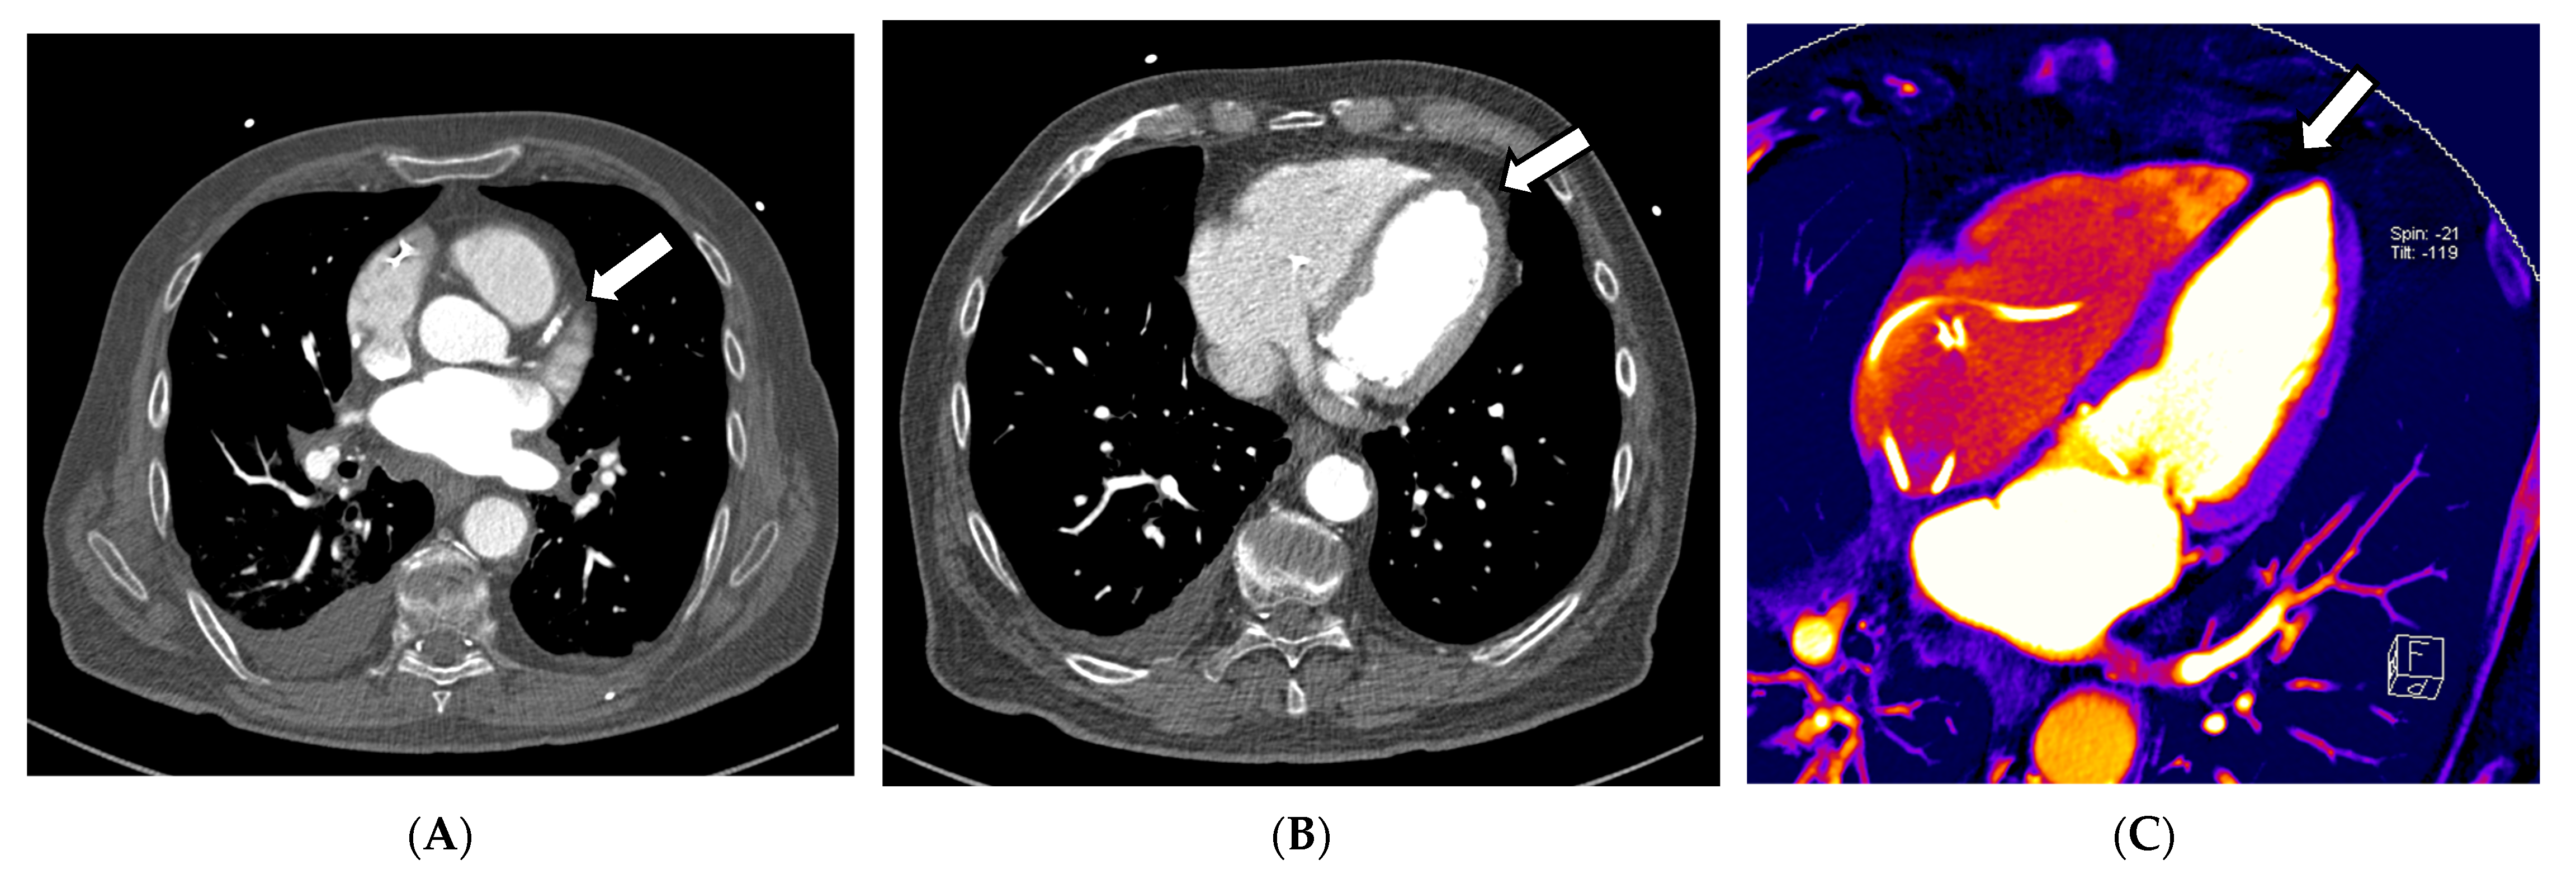

Applications such as color-coded VNCa enable improved visualization of disc herniation (see Figure 4A–D). In 2021, Koch et al. evaluated the diagnostic sensitivity, specificity, and accuracy of color-coded VNCa for the detection of thoracic disc herniation. They found that DECT was significantly better in the tested categories than conventional CT, with a sensitivity of 95% in DECT vs. 73% in SECT and a specificity of 96% in DECT vs. 82% in SECT [64].

Figure 4.

DECT scan of the thoracal spine in a 61-year-old female patient that presented herself with focal pain at the upper back in the clinical examination after slipping and falling on her back. The clinicians suspected a possible vertebral fracture. Thus, a CT scan without a contrast agent was scheduled. During the reading of the images, fractures were ruled out quickly. In the VMI 120 kV soft tissue kernel CT reconstruction, as shown in (A) axial and (B) in sagittal orientation, disk herniation was hardly visible. Application of color-coded VNCa DECT reconstructions finally revealed dorsal median disc herniations (indicated by the white arrows in (D,F)) in segments T 6/7 and T 7/8, as seen in (C) in axial orientation and (D) in sagittal orientation. The finding was later verified in a 1.5 Tesla MRI examination, where the disc herniation could be correlated to the CT findings, as seen in the axial T2-WI sequence (E) and the sagittal T2-WI sequence (F).